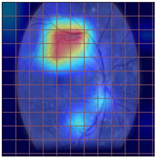

3.2. Models Explainability on the Test Set

| Original Image | VGG16 | ResNet-18 | DenseNet-121 |

|---|---|---|---|

![]() | ![]() | ![]() | ![]() |

| (a) | |||

| (b) | |||

| (c) | |||

| (d) | |||

| Model | Conformity with Normal Retinal Photos | Conformity with Abnormal Retinal Photos | Average Conformity |

| VGG16 | 0.2000 | 0.2414 | 0.2207 |

| ResNet-18 | 0.0294 | 0.0645 | 0.0469 |

| DenseNet-121 | 0.0385 | 0.0286 | 0.0336 |